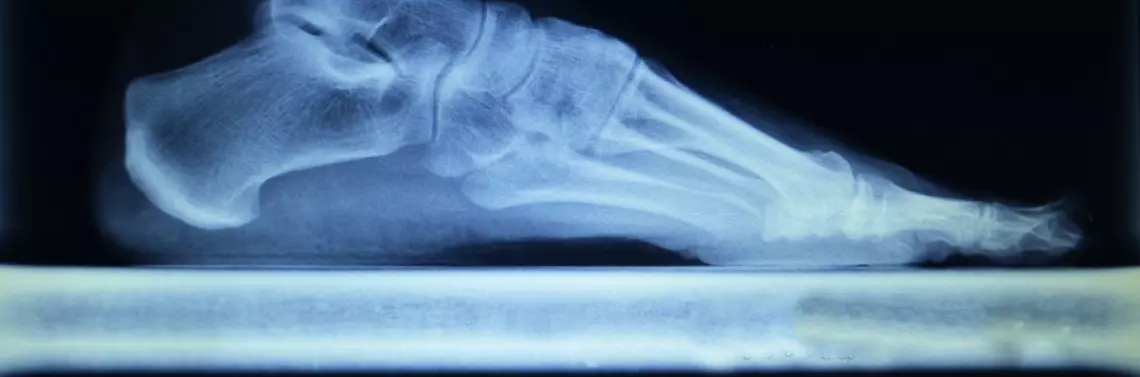

Pedobarografia to obiektywne narzędzie przydatne zarówno w procesie diagnostyki parametrów czasowo-przestrzennych istotnych determinant ruchu, jak i ocenie stabilometrii oraz symetrii ciała. Badanie, które (pomijając czynności wywiadu oraz dodatkowej oceny funkcjonalnej narządu ruchu, której nie da się pominąć) trwa nie dłużej niż 1,5–2 min. Często uzyskane wyniki są analizowane w dalszych etapach terapii ze względu na ograniczenia czasowe, nierzadko bowiem z trudem udaje się wykonać usługę diagnozy fizjoterapeutycznej w ciągu godziny. Pedobarograf zintegrowany z komputerem, zwykłą kamerą internetową i oprogramowaniem przeznaczonym do przetwarzania oraz obliczania biomechanicznych parametrów (tu: Biomech Studio) pozwala wykonać wiele (dotychczas nieosiągalnych) pomiarów. Służy zarówno do wstępnej oceny pacjenta, jak i obiektywnej ewaluacji postępów terapii. Analiza efektywności ma ogromne znaczenie nie tylko z punktu widzenia odpowiedzialności za podejmowane czynności. Ró...